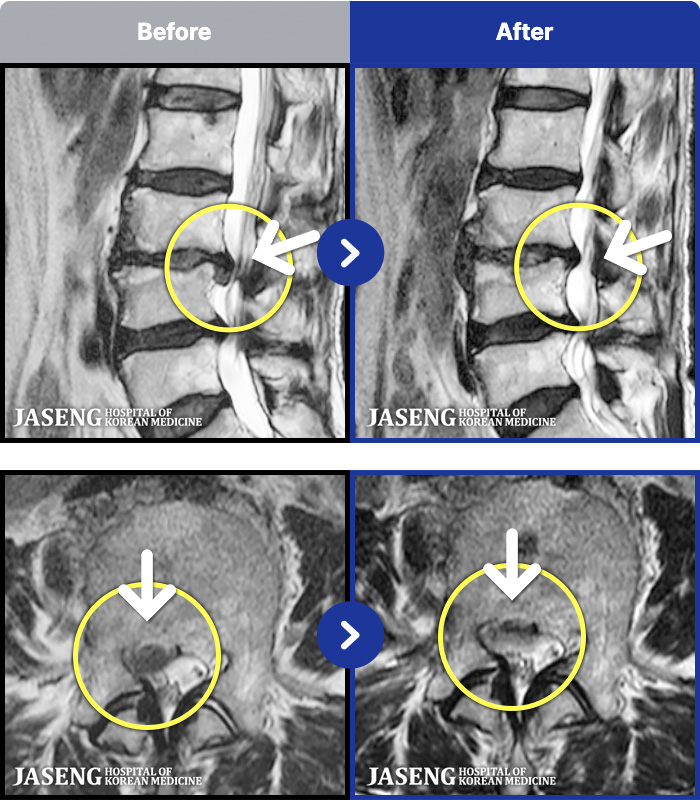

1,286 MRI ũ ʸ Ȯϼ.

[ϻ] 24.07.25~25.08.01